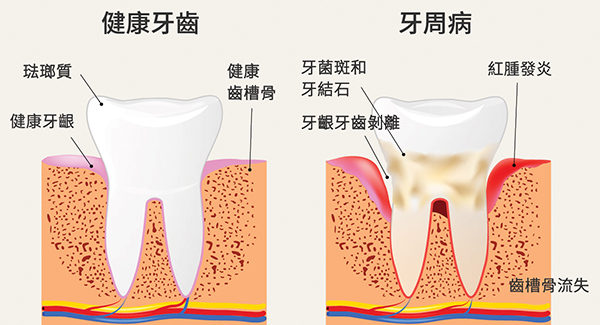

【黎医生教室1】华人好发的口腔疾病──牙周病

你刷牙时会流血吗?牙龈红肿吗?抱怨洗牙后吃东西开始塞牙缝还不如不洗吗?想当然认为人老了掉牙是正常现象吗?……如果以上任何一条说中了你,那么你可能罹患了好发于华人的口腔疾病──牙周病(Periodontal Disease)。

据卡城西北区Beddington Dental Clinic的牙科医生黎医生(Lawrence Lai)介绍,在他20年的从业过程中,所接触的白人患者10人中不到1人有牙周病,但华人牙周病的比例高达3成。一是因为华人群体某些遗传因素增加了个体对牙周病的易感性,二是华人本身没有洗牙的习惯,导致菌斑、牙石沉积,进而引发牙周病。

什么是牙周病?

黎医生形容,牙齿如同一颗大树,张口看见的部分是树冠和树干,看不见的部分──树根,扎在牙床(包括牙龈、牙槽骨)里。大树挺立,是因为根深且固,一旦根周的泥土流失,树即倾倒,牙齿就松动甚至脱落了。

牙周炎是牙周组织(泥土)发生炎症、遭到破坏的疾病。长期不受控制的牙龈炎慢慢扩散到牙周膜,牙槽骨。牙周组织慢慢萎缩,如同泥土的流失。

牙周病随着患者年龄的增大而越趋严重。年龄越大,累积摄入的食物越多,再加上不洗牙,食物残渣堆积在齿缝间,菌斑丛生,牙周病就不可避免了。

牙周病一般从20岁后开始发生,过了50岁,风险明显增大。

牙周病有什么症状?

黎医生表示,牙周病最初并无任何症状,继而会出现牙龈发红、肿胀、疼痛,刷牙时开始流血。此时,牙槽骨完好,只是牙龈发炎,通过洁牙洗牙可以治愈。

如果不治疗,任由发展,经过10-20年,炎症进一步发展至深部,将导致牙槽骨萎缩,骨面下降,从1毫米,到2毫米,到3毫米……牙槽骨萎缩后,出现的空间由牙龈肿胀而填充,外表看起来牙齿紧密,没有缝隙,但实际上骨头与牙龈的比例已经改变了。牙槽骨继续萎缩下去,牙龈无法再填充时,牙齿间便出现了缝隙,牙周袋也渐渐形成了。

不同于牙龈发炎,牙槽骨萎缩后,病变无法回复,不能根治,治疗手段的作用只是阻止病变进一步发展,但已经消失的骨头不会再长回来了。